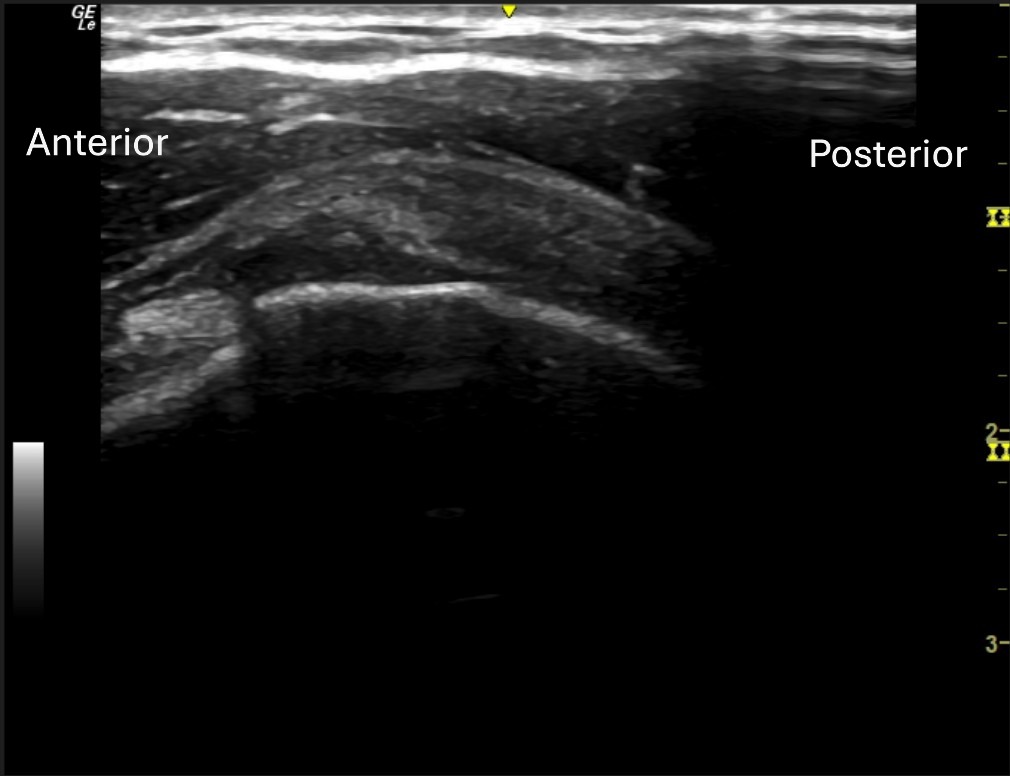

Unlabeled long axis view of the posterior supraspinatus at the articular surface.

Unlabeled long axis view of the anterior supraspinatus tendon at the articular surface.